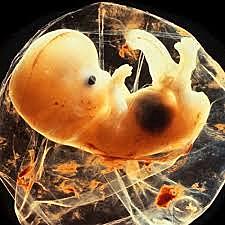

• Blastocisto

5

Blastocisto

Compactación de las células totipotenciales y constitución de trofoblasto, blastocele y nodo embrionario